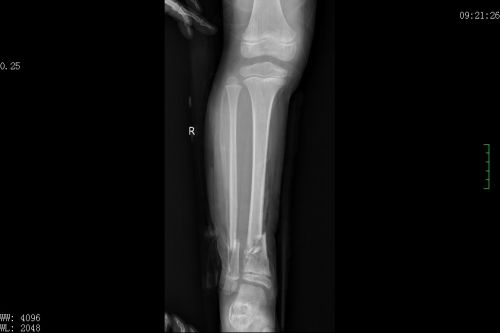

术前x片显示,右侧胫腓骨粉碎性骨折。